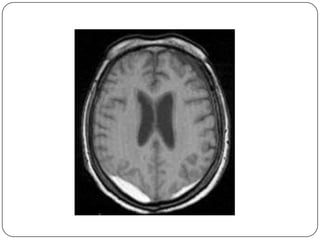

Hematoma Subdural

 Sangre entre la dura y la aracnoides

 No hay relacion con fracturas

 Forma semilunar

 Cruza las suturas, pero no las inserciones

durales

 T.A.C. fase aguda = coleccion hiperdensa

 I.R.M.detecta hematomas muy pequenos

Hematoma Subdural  Sangreentre la dura y la aracnoides  No hay relacion con fracturas  Forma semilunar  Cruza las suturas, pero no las inserciones durales  T.A.C. fase aguda = coleccion hiperdensa  I.R.M.detecta hematomas muy pequenos

Hueso dura aracnoides pia Cerebro Hematoma subdural concavo en su margen interno